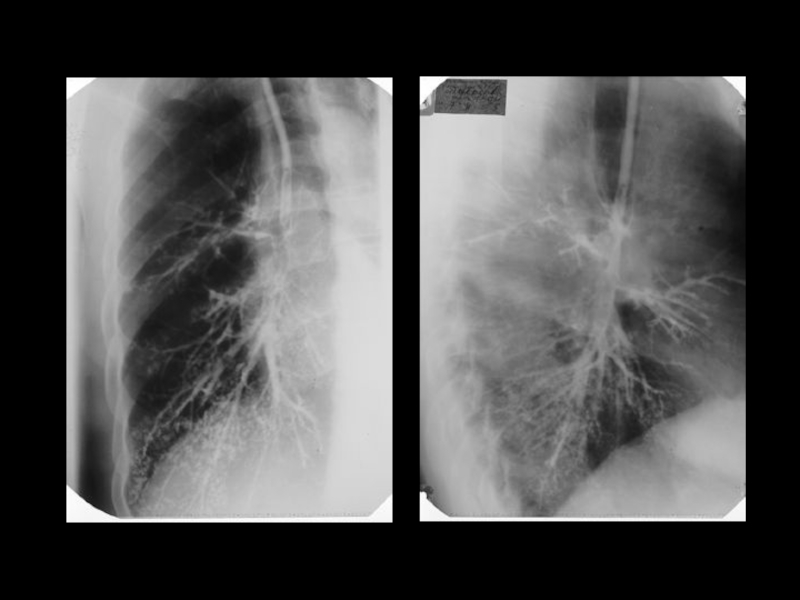

Центральный рак легкого

ЛУЧЕВАЯ ДИАГНОСТИКА РАКА ЛЕГКОГО